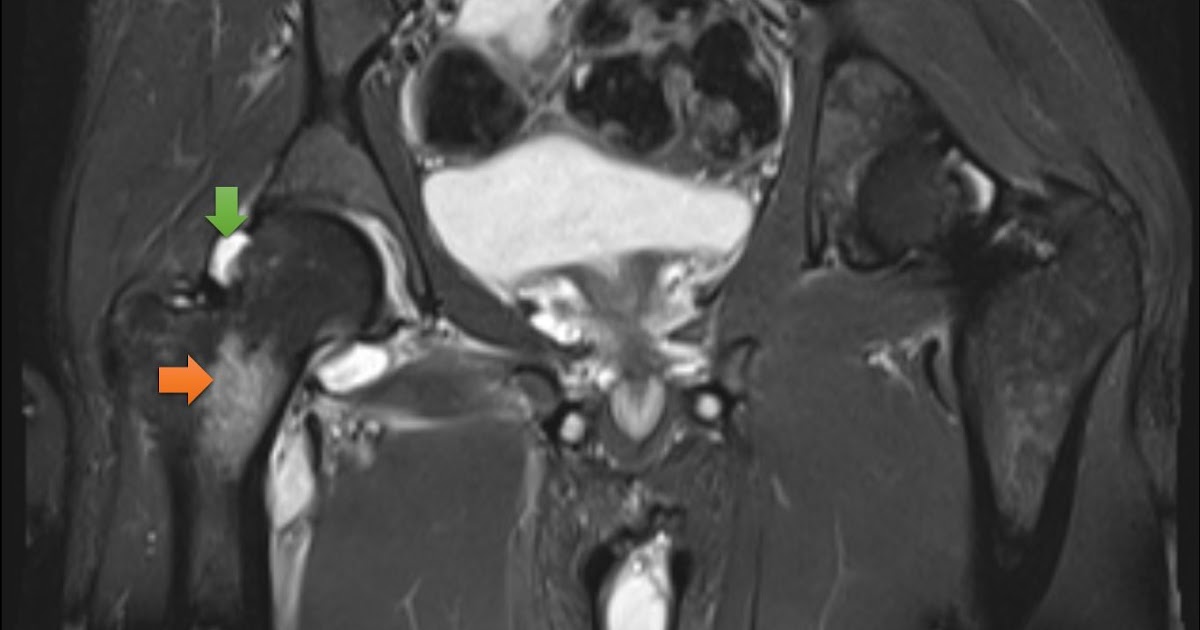

From www.svuhradiology.ie

Septic arthritis hip Radiology at St. Vincent's University Hospital Septic Arthritis Joint Replacement A delay in diagnosis and. Other treatments include medicines for pain and. septic arthritis should be considered in adults presenting with acute monoarticular arthritis. the epidemiology, microbiology, clinical manifestations, diagnosis, differential diagnosis, and treatment of. quick treatment with antibiotics for bacterial septic arthritis is needed to halt the risk of joint damage. If you get septic arthritis. Septic Arthritis Joint Replacement.